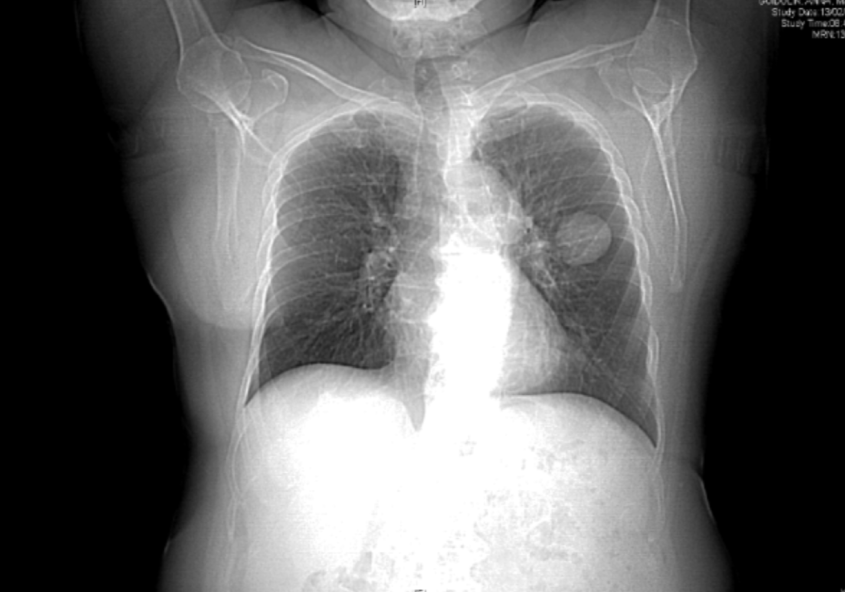

TERAPIA CON ANTI-ORMONI IN UN SUBDOLO CASO DI PNX CATAMENIALE

Lo pneumotorace (PNX) catameniale, l’espressione patologica più frequente dell’endometriosi toracica, è la patologia affrontata in questo articolo: attraverso l’analisi di un caso clinico, si giunge alla conclusione che la cura più indicata è la chirurgia con asportazione delle isole di endometriosi.